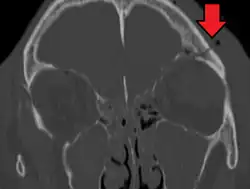

Basilar skull fracture

| A subtle temporal bone fracture as seen on a CT scan | |

A basilar skull fracture is a break of a bone in the base of the skull.[1] Symptoms may include bruising behind the ears, bruising around the eyes, or blood behind the ear drum.[1] A cerebrospinal fluid (CSF) leak occurs in about 20% of cases and may result in fluid leaking from the nose or ear.[1] Meningitis occurs in about 14% of cases.[2] Other complications include injuries to the cranial nerves or blood vessels.[1]

A basilar skull fracture typically requires a significant degree of trauma to occur.[1] It is defined as a fracture of one or more of the temporal, occipital, sphenoid, frontal or ethmoid bone.[1] Basilar skull fractures are divided into anterior fossa, middle fossa and posterior fossa fractures.[1] Facial fractures often also occur.[1] Diagnosis is typically by CT scan.[1]